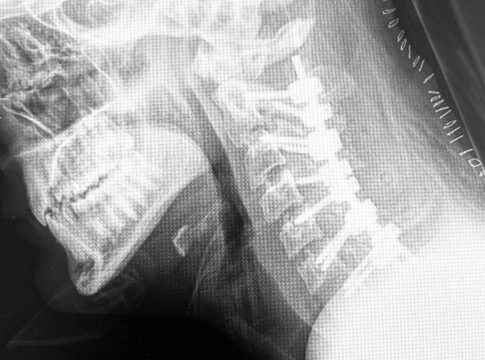

La cifosis post-laminectomía cervical es una curvatura anormal hacia adelante de la columna cervical (cuello) que puede ocurrir después de una laminectomía, que es un tipo de cirugía de columna. Esta condición puede resultar de la eliminación de parte de la lámina, que es una estructura ósea que cubre y protege la médula espinal, lo que puede alterar la estabilidad y la alineación de la columna vertebral. La gravedad de la cifosis y los síntomas asociados pueden variar y, en consecuencia, las estrategias de tratamiento también

Fusión Espinal: Unir dos o más vértebras utilizando injertos óseos y/o dispositivos de fijación como tornillos y barras para estabilizar y corregir la alineación de la columna vertebral.